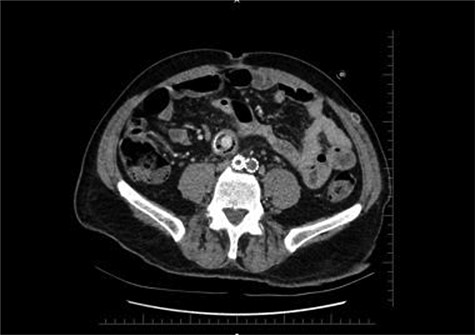

Distal CT axial section shows the two limbs of the EVAR, at the bottom. And on top of it, the Dacron straight graft part in the middle of the jejenum.

During the first days of December 2018, the patient visited another medical center because of fatigue, difficulty in breathing, lower back pain and inability to walk. His blood biochemistry revealed a very high CRP level (350 mg/dl), and complete blood count revealed a very high level of white blood cells (21 000/ul). An abdominal CT scan illustrated part of the graft was totally eroded into the small intestine (Figs 1–3). The patient was referred to my office and an infectious disease specialist. He had high body temperature (39.5°C) and was lying on the bed with lower extremities adducted to the chest. Antibiotic and supportive treatment was started. Emergency surgery was performed. We found an 8–10 cm of the straight part of the graft had become totally incorporated into the proximal part of the jejenum. The graft was freed, and 10–15 cm of the jejenum was resected and anastomosed. The area was irrigated with saline and hypochlorous acid. We then put a 20 x 10 composite mesh between the vascular graft and the intestine using a non-adhensive surface facing the intestine to prevent future graft and intestine interactions and erosion. After hemostasis, two drains were placed retroperitonally, and the abdomen was closed. On the fourth post-operative day, a high body temperature and high CRP levels were recorded. An abdominal CT revealed retroperitoneal abcess formation. During relaparotomy, the anastomosis was found to be intact, and the retroperitoneal abscess was drained and irrigated with saline. The drains were reinserted. After a month, he once again started to have high fever and high CRP levels. Again, an abdominal CT revealed abscess formation. This time, the abscess was approached transcutaneously. By making an incision in the proximal left lomber region, the abscess was drained. Another incision was made distally, and two drains were placed in the retroperitoneal area.